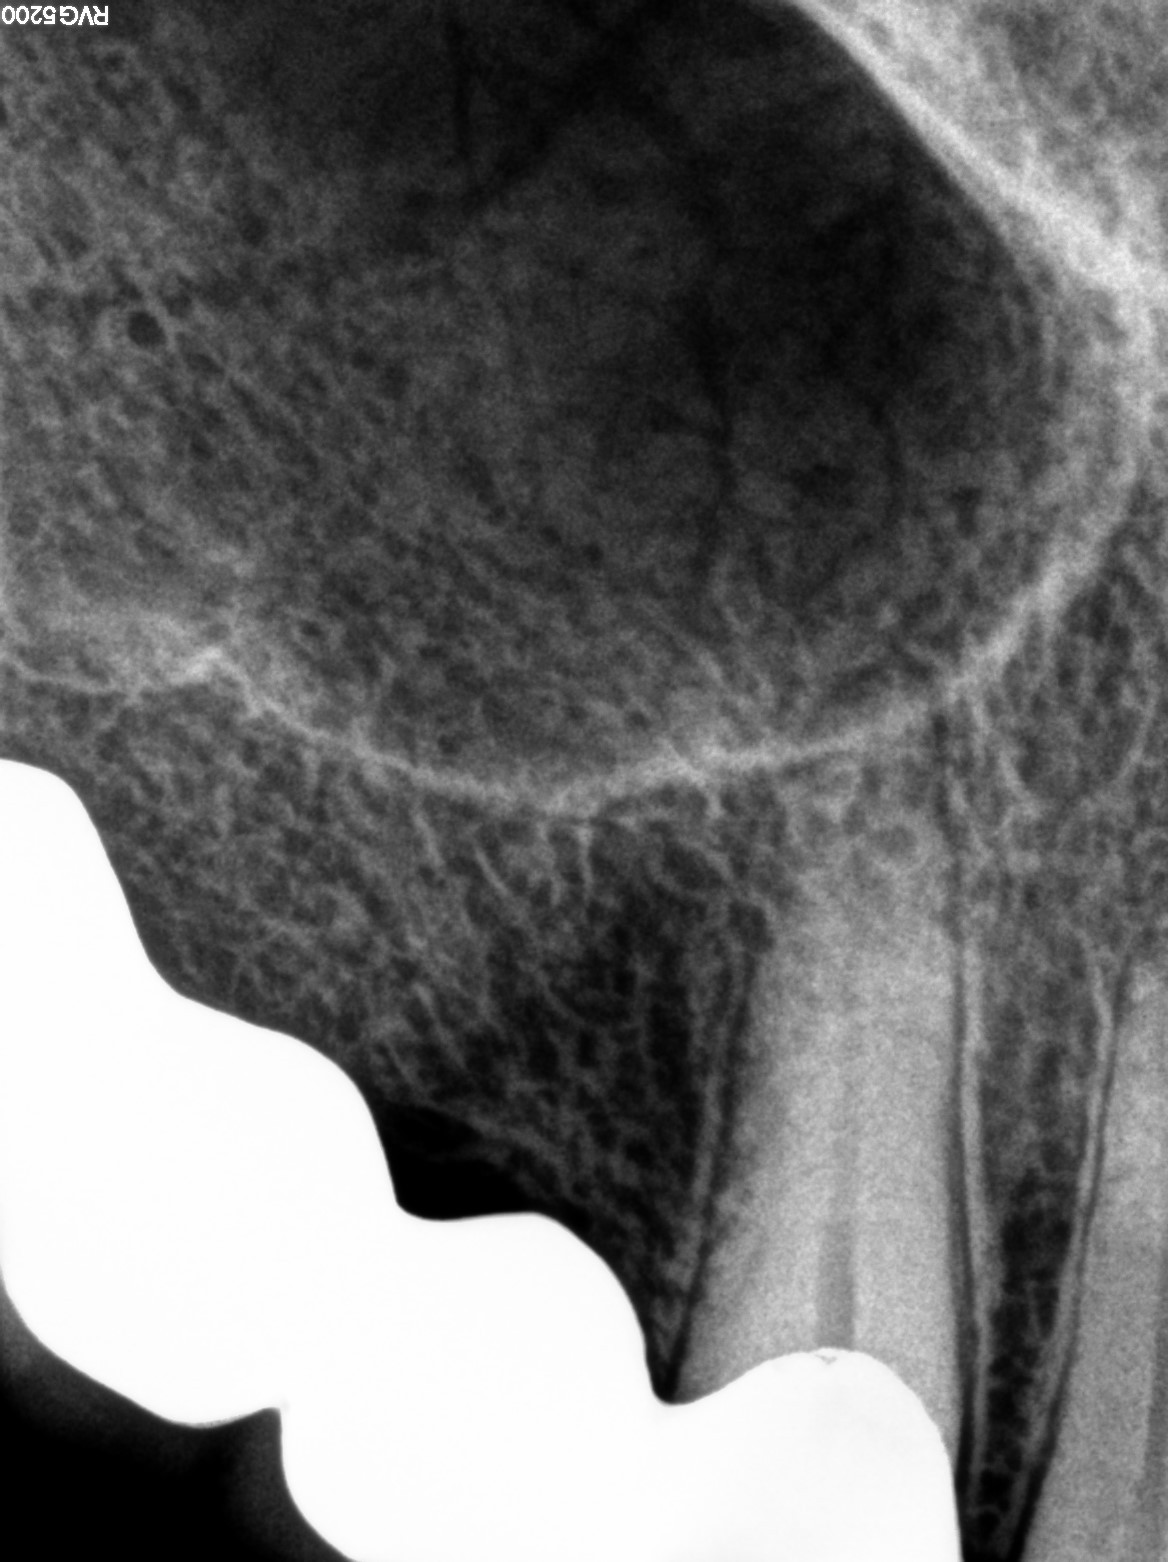

Dental Radiographs FHIR: DocumentReference · LOINC 24641-7

xray_1764234367_1.jpg

24641-7